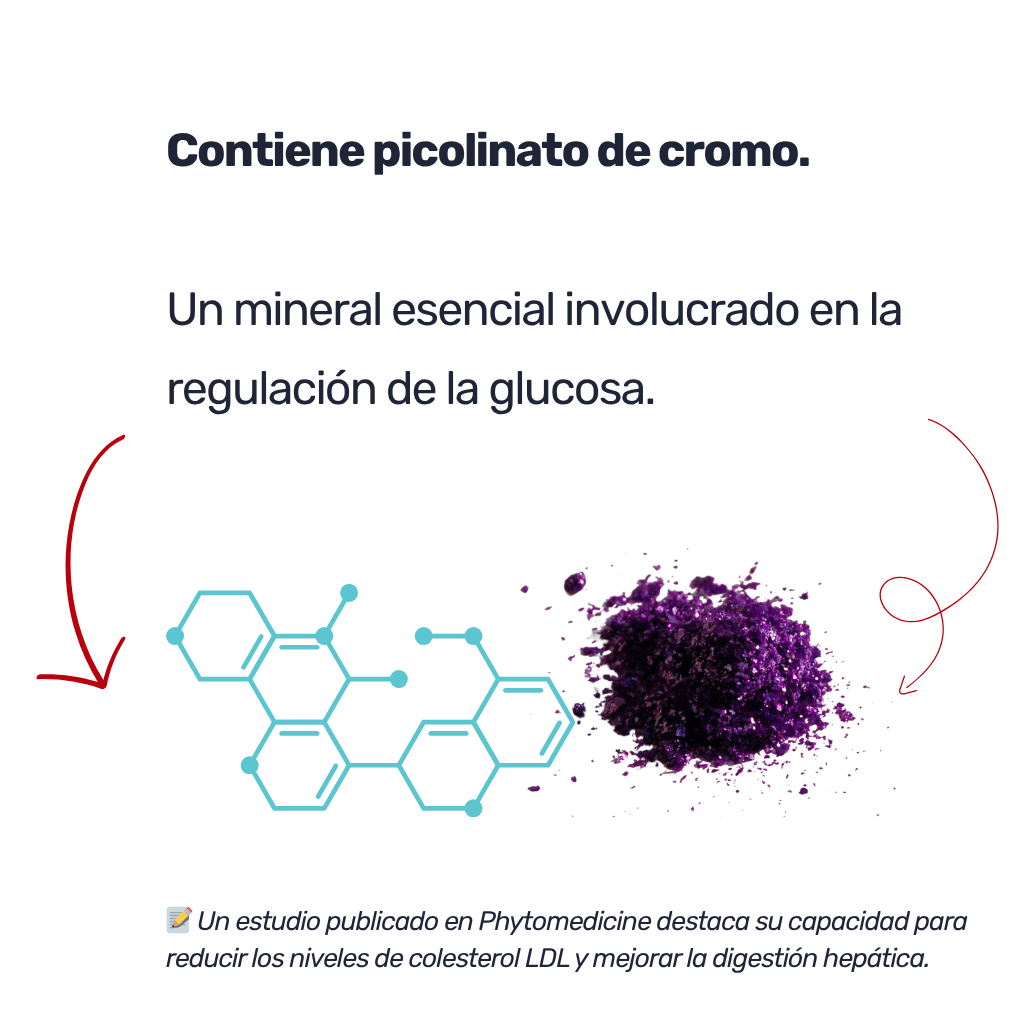

Suplemento en cápsulas con cromo, pensado para complementar rutinas de alimentación moderna. Ideal para quienes siguen dietas específicas o buscan incluir este mineral esencial como parte de su bienestar diario.